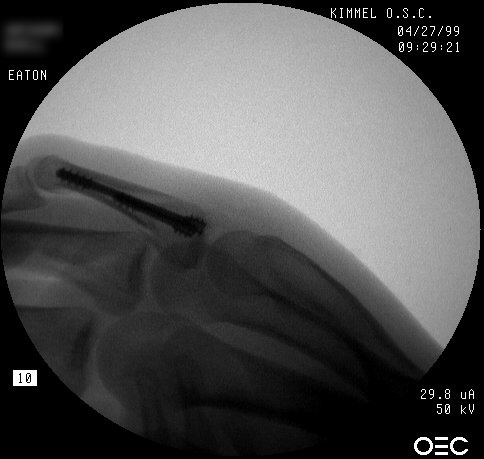

| Proximal phalanx fractures are a common problem with many treatment options. These images illustrate a technique of stabilization using intramedullary Herbert screws placed percutaneously through the base of the proximal phalanx. Provisional fixation is obtained with K wires which are replaced with Herbert screws, which simply follow the soft tissue path of the pin tract to the bone. Self tapping screws are not used in this technique, as the cutting threads catch on soft tissues. |

| A second case, five weeks after injury with early callus, treated with similar technique after percutaneous fracture mobilization with a small elevator. |